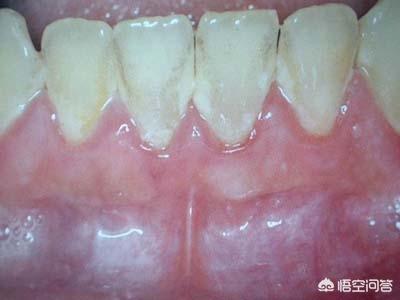

临床以微生物感染造成牙周炎症性出血,进而引起结缔组织和骨破坏为主要表现。牙周病造成的组织损害是不可逆的,如果不经过专业、系统的治疗非但不能自愈反而会愈发严重导致最后牙齿丧失支持松动脱落。

牙菌斑是牙周病的使动因子。对口腔卫生不重视,不正确的刷牙方法,不良的修复体等易造成牙菌斑堆积、钙化形成牙石长期刺激牙周组织引发牙周病。同时牙周病还是一些慢性消耗性疾病的并发症(如糖尿病)之一。

2、牙龈红肿程度比较严重,如果是牙龈炎,牙龈最多红红的,有时候刷牙可能会出血,但是牙周炎的话,肿胀可以看得出来,尤其是牙龈乳头经常有不适感,简单来说牙龈萎缩,牙根暴露强烈酸痛。